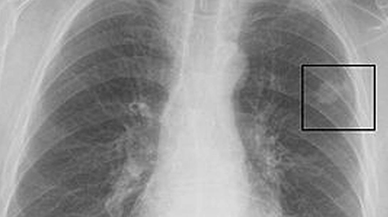

Akciğerde Leke Haberleri

Son Dakika Akciğerde Leke Haberleri

Bu sayfada güncel gelişmeleri takip edenler için Akciğerde Leke ile ilgili en son gelişmeler ve son dakika Akciğerde Leke haberleri sunulmaktadır. Akciğerde Leke videoları, Akciğerde Leke fotoğrafları ve Akciğerde Leke haberleri